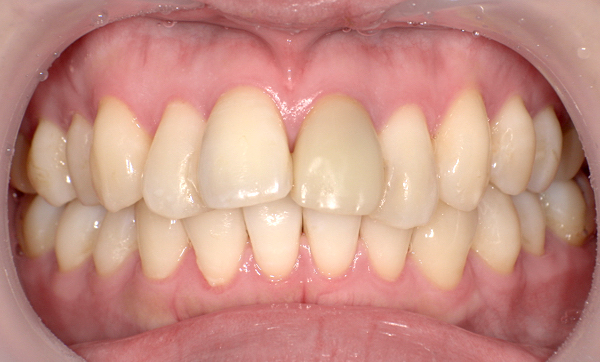

症例_010 「出っ歯」症例

治療期間:7ヶ月金額:30万円+税20代女性出っ歯捻転歯上の前歯だけ

| Before | After |

|---|---|

|